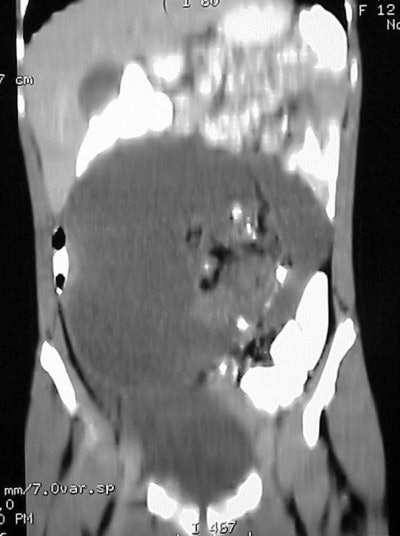

In figure TC 3 we can see a large soft-tissue mass measuring approximately 9 cm wide by 6 cm in AP diameter, and 14 cm in height. It contains both fluid and semi-solid components of soft tissue as well as assorted calcifications. The mass appears to terminate (Figure TC 4) just above the level of the uterus (arrow).

The images (Figures TC 5 and TC 6) show, respectively, a sagittal and coronal MPR of the axial images, demonstrating the size and volume of the structure.